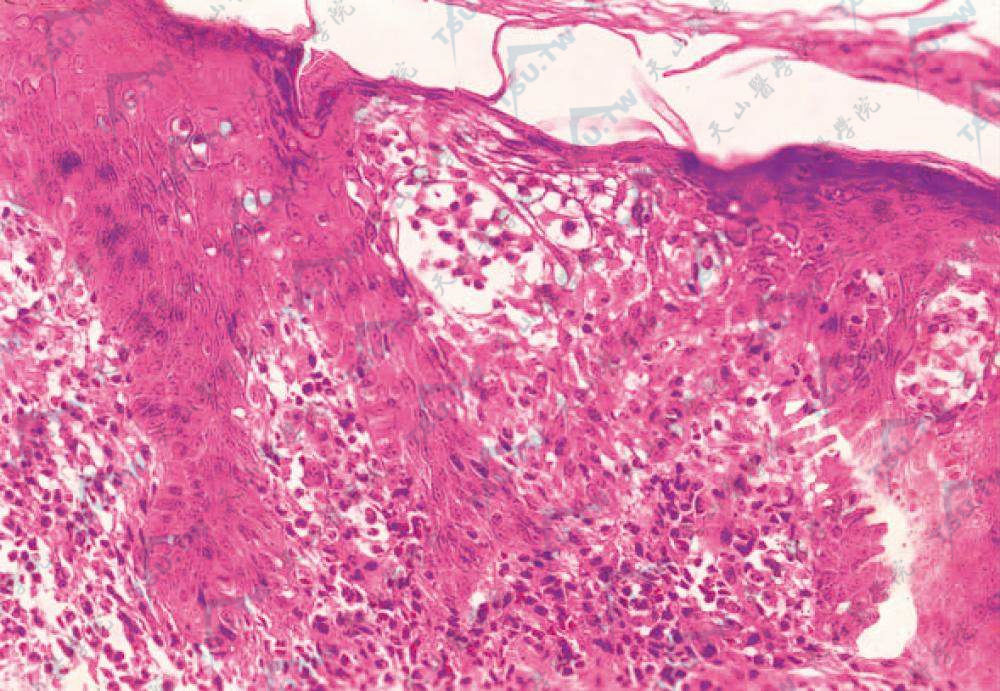

早期蕈样肉芽肿的组织病理学诊断标准